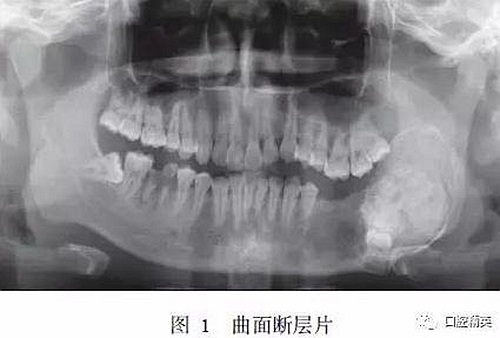

入院時(shí)專科查體:患者面型不對(duì)稱,開口度正常,開口型偏左側(cè)。左下頜膨隆明顯,范圍約5.0 cm×3.0 cm,向前延伸至D5根尖處,向后延伸至下頜升支,質(zhì)硬,觸之無乒乓樣感??趦?nèi)檢查示D5~D8缺失,左側(cè)頜下有一腫大淋巴結(jié),質(zhì)硬,活動(dòng),大小約1.5 cm×1.5 cm。曲面斷層片示:左下頜D4根尖區(qū)至左下頜升支乙狀切跡下方可見一異常高密度團(tuán)塊影,團(tuán)塊中心密度不均勻,病變邊緣光滑,周緣可見低密度條帶影包繞,D5~D8牙埋伏阻生于病變內(nèi),似不規(guī)則小牙體征象,病變區(qū)頜骨向頰舌向膨隆明顯,下頜神經(jīng)管受壓后向下移位(圖1)。

錐形束CT示:左下頜D5~D7缺失,D5~D7位置下頜骨內(nèi)可見牙瘤樣結(jié)構(gòu),左下頜骨膨隆明顯,膨隆向上至下頜骨升支乙狀切跡下方,向下至下頜骨下緣,向前至下頜骨體D5位置,向后至下頜升支中份,骨質(zhì)膨隆內(nèi)可見鈣化程度不同的阻射影(圖2)。